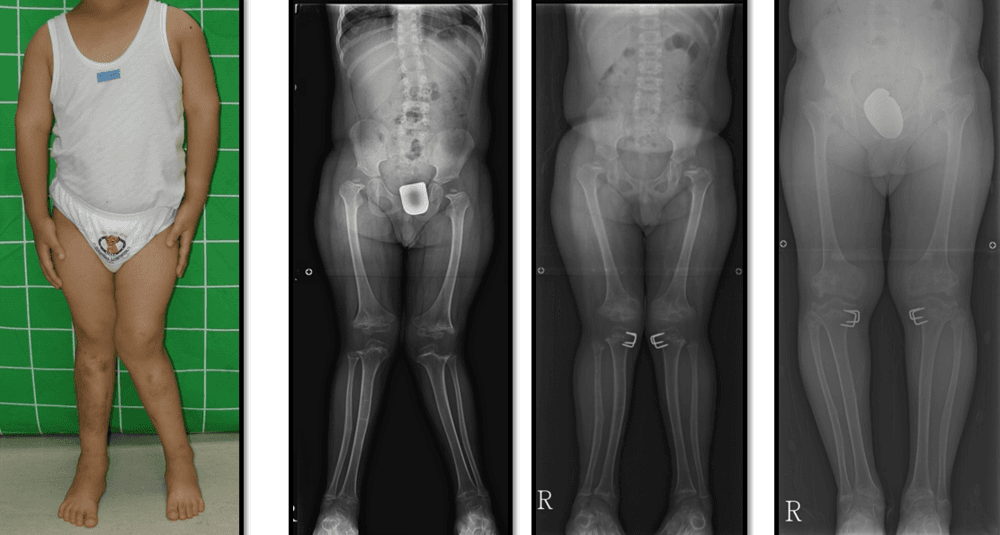

연골무형성증환자의 하지변형에 대한 교정

가성연골무형성증환자의 하지변형에 대한 교정